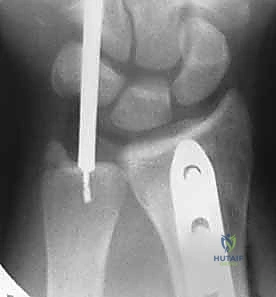

4. التثبيت الداخلي (Internal Fixation)

يتم استخدام شريحة معدنية قوية (Compression Plate) ومسامير لتثبيت العظم بقوة. هذه الشريحة تعمل كجسر يحمل العظم حتى يلتئم تماماً.

5. تقييم وتثبيت مفصل الكعبرة الزندي البعيد (DRUJ)

هذه هي الخطوة الأهم التي تميز الجراح الخبير. بعد تثبيت الكعبرة، يقوم الدكتور هطيف بفحص استقرار مفصل DRUJ.

* إذا كان المفصل مستقراً: لا حاجة لتدخل إضافي.

* إذا كان المفصل غير مستقر (يُخلع عند دوران الساعد): يتم تثبيته باستخدام أسلاك معدنية دقيقة (K-wires) تُترك لمدة 4 إلى 6 أسابيع، وقد يتطلب الأمر إصلاحاً مباشراً لأربطة TFCC الممزقة.